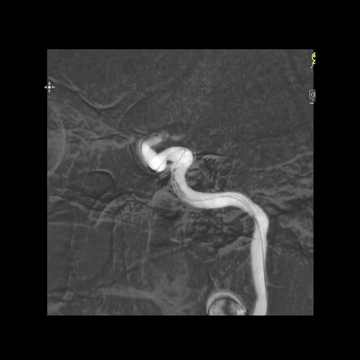

5F多功能管(125cm)+6F长鞘(90cm,Cook)组成同轴,泥鳅导丝导引下,快速过弓,把长鞘头端送至右侧颈总动脉远端,造影见溶栓后栓子迁移至M1远端;泥鳅导丝导引5F中间管克服C1段迂曲,上高到海绵窦段,同时尽量上高长鞘增强支撑。

中间管内衬.018"导丝(Command 18),并尽力推高长鞘,在增强支撑下把中间管头端推送至颈内动脉末端,以增加对微导管微导丝的支撑性。